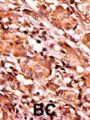

Applications WB, IHC-P

IHC: 1:50-100